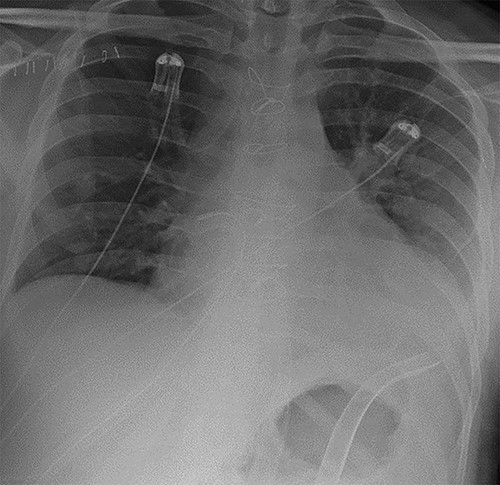

A 38-year-old Caucasian male presented to hospital with shortness of breath. He was diagnosed with dilated cardiomyopathy following transthoracic echocardiography. He continued to deteriorate and developed florid pulmonary oedema as demonstrated in Fig. 1, necessitating his transfer to our centre for further management. Prior to this presentation he had no known comorbidities.

Chest radiograph demonstrating pulmonary oedema prior to implantation of biventricular assist device.